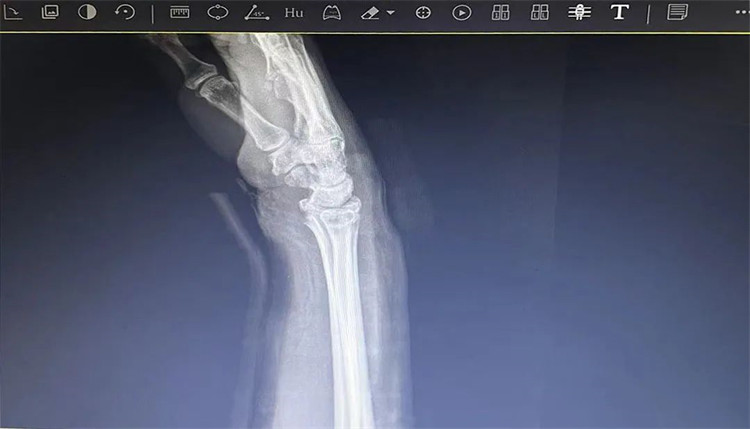

患者老年女性,50多歲,在騎電動車停下時因電動車倒下,右手著地,當(dāng)即感覺,右腕及骶尾部腫痛伴右關(guān)節(jié)畸形、活動受限,急來我院就診。門診醫(yī)師結(jié)合病史、查體及輔助檢查后,診斷為:右橈尺骨遠端骨折、骶尾部挫傷并收入住院部。

患者入院后,中醫(yī)正骨科副主任鄭斌斌,認真查體及分析檢查結(jié)果后,考慮患者老年女性,建議患者采用拔伸牽引、端提、捺正等閉合手法復(fù)位后,行夾板固定,多能獲得較好療效?;颊邚?fù)位固定后,疼痛明顯減輕。避免了手術(shù)帶來的痛苦及手術(shù)開刀所需費用。